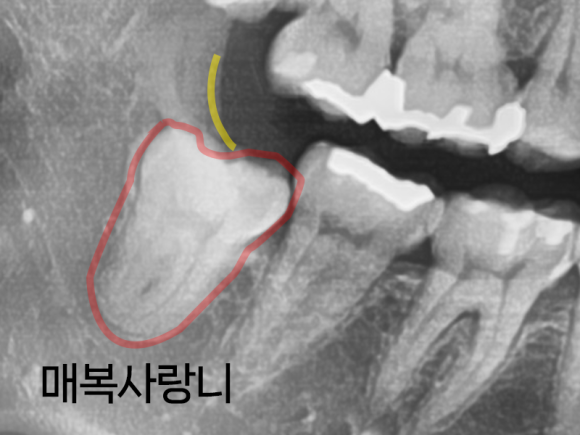

먼저 맹출 상태와 각도, 방향을 살펴봐야 합니다.

사랑니가 똑바로 올라오고 있고

완전히 턱 밖으로 나올 가능성이 있다면

서둘러 뽑지 않고 지켜보는 경우도 있습니다.

이해를 돕기 위한 사진입니다.

하지만 사랑니가 비스듬히 나와있거나

부분적으로만 맹출 되어 있는 경우,

혹은 사랑니의 일 부분이 잇몸 조직이나 점막으로 덮여있는 경우

뼈와 다른 치아에 영향을 주는 경우에는

나이와 상관없이 발치를 합니다.